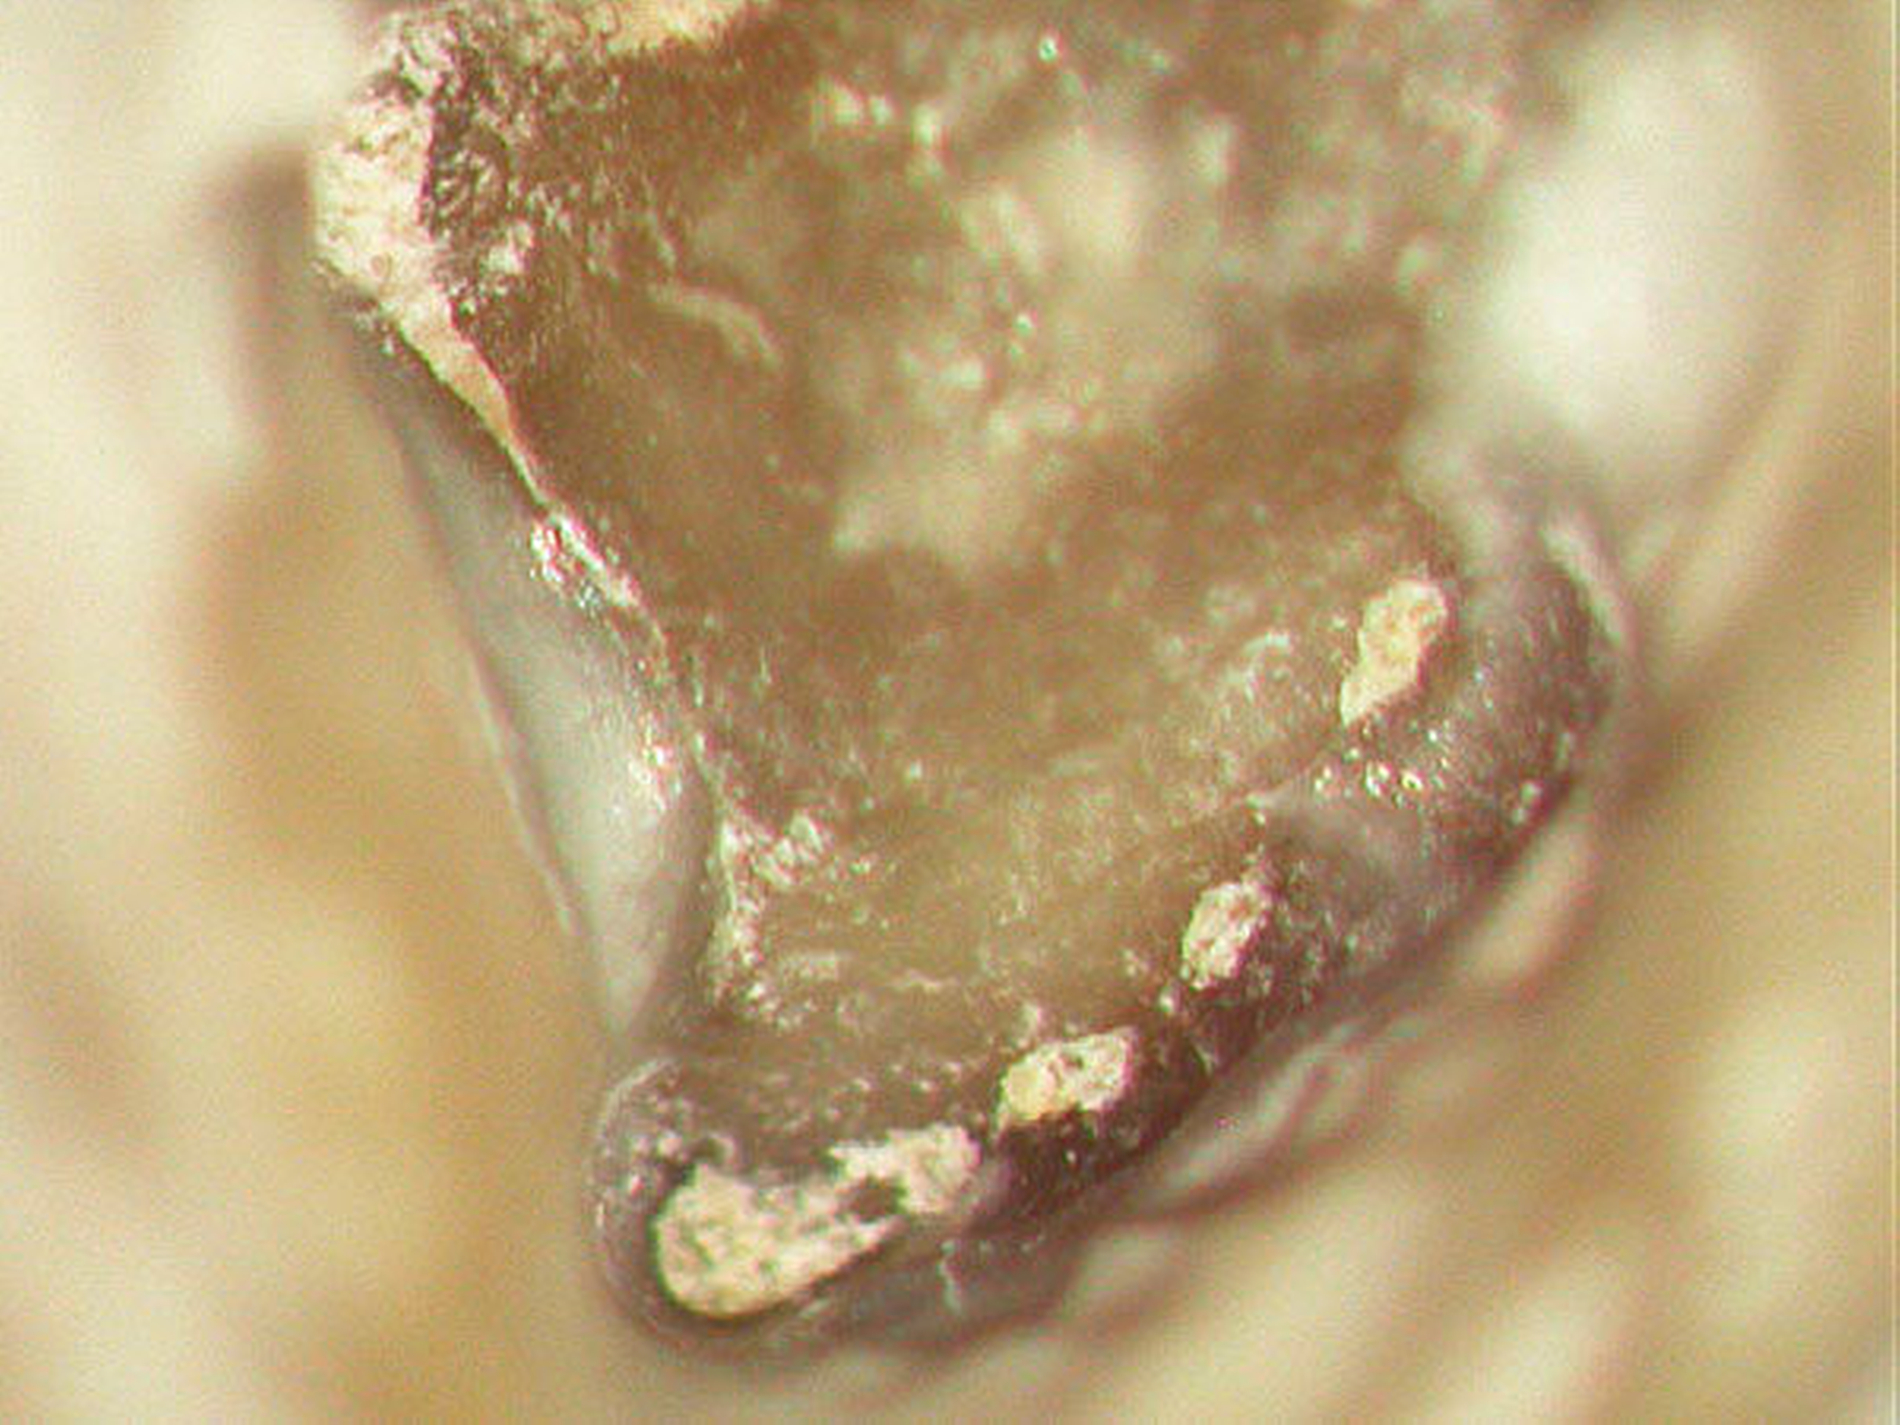

Angaben zu einer Mindestgröße von Wurzelkanälen, die eine mikrobielle Infektion und einen pathologischen Prozess ermöglichen, gibt es nicht. Tatsache ist jedoch, dass scheinbar obliterierte Wurzelkanäle immer noch um ein Vielfaches größer sind als pathologische Mikroorganismen (Abbildung 9).